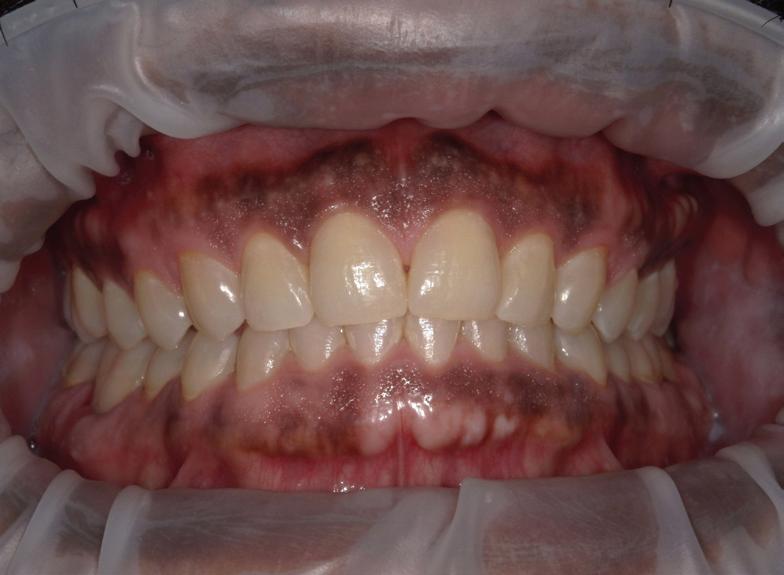

Submitted By Sivakumar Sreenivasan, DMD, MDS Dental Implant Center of Rockville

Can just four implants replace all of the teeth on the top or the bottom of your mouth? Thanks to advances in dental implant technology, that answer is a resounding yes.

Tooth loss is extremely common among adults, especially as we age. Rather than living with the discomfort and hassles of dentures, many people are opting for what is called “all-onfour” dental implant restoration.

An implant is a small titanium

screw that fits inside your jawbone and replaces the root-part of a missing tooth. Minor surgery is required to insert the implants. Once the implant is in place, a crown is attached to give you a highly realistic-looking and functional prosthetic tooth.

You do not need a dental implant for each and every one of your missing teeth. All you need is four precisely placed implants on the top of your mouth, and four on the bottom, to restore your full smile. That’s the beauty of the all-on-four. And because the implant is made of titanium, it has the unique ability to fuse to living bone and function as part of it. So eventually, the dental implant becomes part of the jawbone and serves as a strong, longlasting foundation for your new teeth.

Besides ensuring that your implants are permanently fixed in place, this bone fusion has another important benefit: it prevents future bone loss in the jaw. This helps to maintain a more youthful facial structure – and better